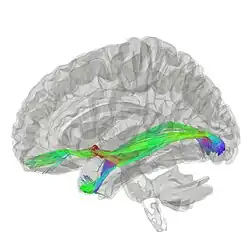

La commissure antérieure, appelée également la commissure blanche antérieure ou encore la précommissure (en latin : commissura anterior), est une commissure inter-hémisphérique qui croise transversalement la paroi antérieure du troisième ventricule[1]. C'est un faisceau nerveux de substance blanche (un paquet d'axones) qui relie les deux lobes temporaux des hémisphères cérébraux à travers la ligne médiane, et il se trouve en avant des colonnes du fornix (les piliers antérieurs trigone du cerveau). Chez la plupart des mammifères existants, la grande majorité des fibres reliant les deux hémisphères traversent le corps calleux, qui est plus de 10 fois plus grand que la commissure antérieure, et d'autres voies de communication passent par la commissure de l'hippocampe ou indirectement, via des connexions sous-corticales. Néanmoins, la commissure antérieure est une voie importante qui peut être distinguée clairement dans les cerveaux de tous les mammifères.

Les fibres de la commissure antérieure peuvent être tracées latéralement et postérieurement de chaque côté au-dessous du corps strié vers la substance du lobe temporal.

Elle sert à relier les deux lobes temporaux, mais il contient également des fibres décussantes des tractus olfactifs, et fait partie du tractus néospinothalamique pour la douleur. La commissure antérieure sert ainsi à relier les deux amygdales.

Le corps calleux permet la communication entre les deux hémisphères, et il ne se trouve que chez les mammifères placentaires (les euthériens), alors qu'il est absent chez les monotrèmes et les marsupiaux, ainsi que d'autres vertébrés tels que les oiseaux, les reptiles, les amphibiens et les poissons. La commissure antérieure sert de mode principal de communication interhémisphérique chez les marsupiaux[2],[3], et c'est elle qui porte toutes les fibres commissurales provenant du néocortex (également connu sous le nom de néopallium), alors que chez les mammifères placentaires la commissure antérieure ne porte que certaines de ces fibres[4].